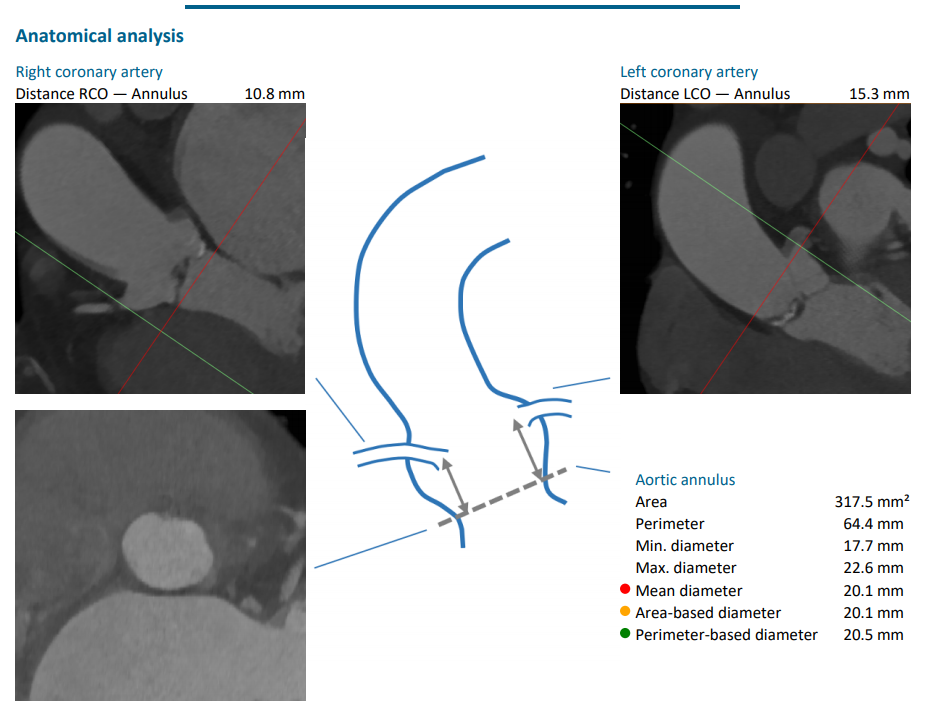

CT评估报告

瓣环平均直径:20.2 mm,左室流出道平均直径:19.9mm

升主动脉(未见)明显扩张,心脏角度:55°

左冠高度:12.5 mm,右冠高度:13.6 mm

Annulus:20.2mm;LVOT:19.9mm

Sinus:25.3mm*25.2mm*24.7mm ;STJ:23mm*24mm

升主:27.6mm*29mm;主动脉成角:55°